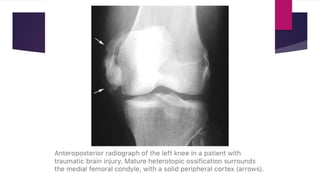

 Radiograph – “Dotted veil” calcification (confusing with

rhabdomyosarcoma or synovial sarcoma). There may be continuous or

discontinuous peripheral calcification.

 Late stage (maturation phase)

 Mass becomes bony hard and easily discernible from its surrounding

tissue.

 Pain reduces dramatically.

 Mass may merge with bone resembling osteochondroma.